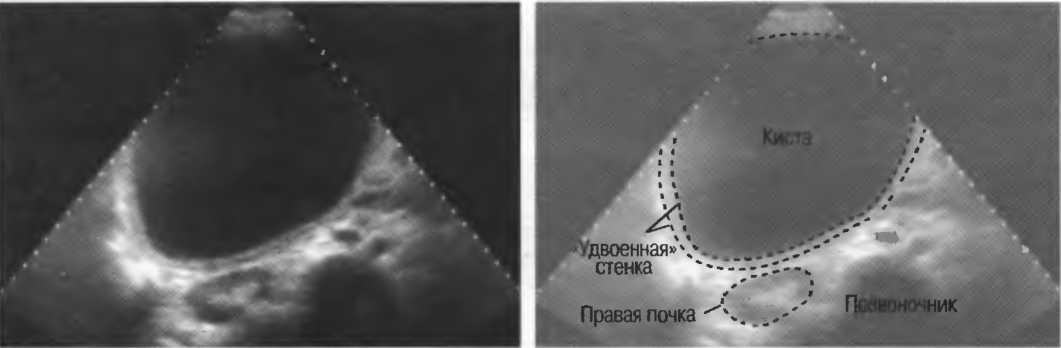

Кисты

Киста, как правило, визуализируется в виде анэхогенной зоны, при этом структуры, расположенные за кистой, обычно усилены: полость кисты анэхогенна, поскольку в ней нет структур с различным акустическим сопротивлением. В результате того что жидкость не поглощает ультразвук в такой же степени, что и ткань, эхо-сигналы от расположенных позади кисты структур гиперкомпенсированы сканером и выглядят усиленными — появляется эффект усиления задней стенки (рис. 14а,б).

Киста определяется в виде анэхогенной зоны с усилением по задней стенке. Если в кисте есть внутренние зхоструктуры, то они могут быть реальными или являться артефактами.

Структура, наподобие содержащей чистую жидкость кисты, визуализируется как анэхогенная зона. Стенки кисты отражают ультразвуковые сигналы под углом, и информация не поступает назад в трансдьюсер. В результате этого появляются боковые тени, но сзади кисты имеется усиление эхосигналов (усиление задней стенки) (рис. 15).

Артефакты могут определяться в любой кистозной структуре (такой, например, как мочевой пузырь или желчный пузырь) и чаще определяются ближе кпереди, становясь менее выраженными на глубине. Они исчезают или меняют свой характер при изменении положения датчика. Но истинные структуры в кисте, такие как перегородки, сохраняют свое местоположение независимо от положения датчика. Истинные отражения имеют место при наличии сгустка крови, гноя, некротической взвеси, и все это чаще визуализируется по задней стенке: если эти структуры не фиксированы к стенке, они изменяют свое положение при перемене положения тела пациента (рис. 16).